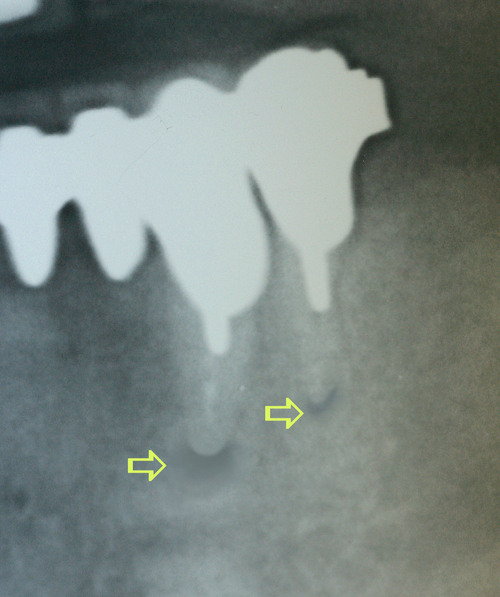

En cas d’infection sous une racine, il est possible de tenter la conservation de cette racine en supprimant cette infection (fig.15).

fig. 15

Infection péri apicale sur les deux piliers de bridge